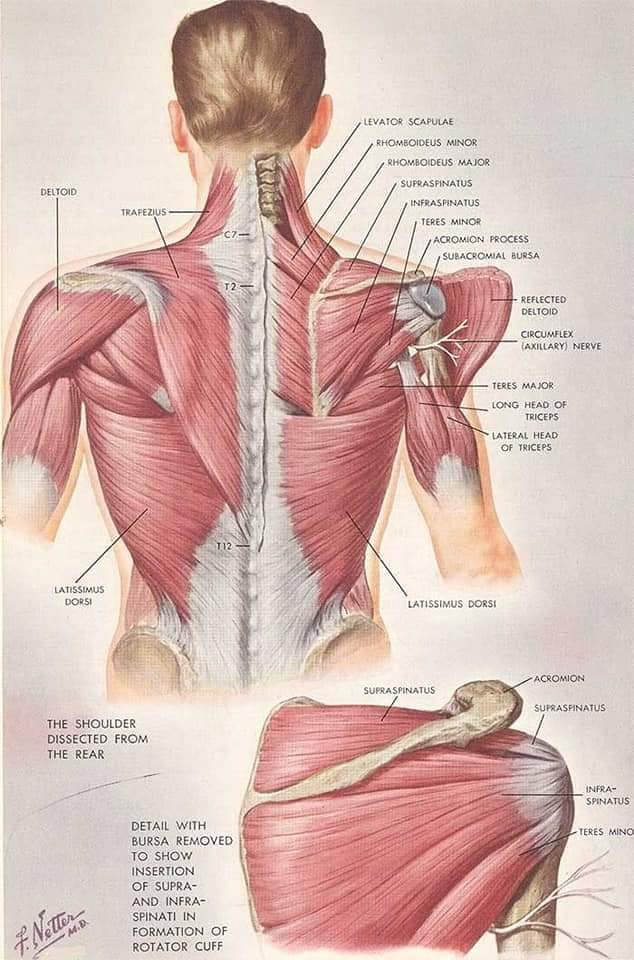

М'язова система людини є однією з основних систем організму, що відповідає за рухи, підтримання пози та стабільність. Вона складається з понад 600 м'язів, які можна класифікувати на скелетні, гладкі та серцеві м'язи. Скелетні м'язи, які є об'єктом нашого детального розгляду, дозволяють контролювати навколишній світ і виконувати різноманітні рухи. Особливу увагу в нашій статті буде приділено шейним і спинним м'язам, оскільки ці групи м'язів мають критичне значення для підтримання правильного постава та функціонування хребта.

Спинні м'язи

Спинні м'язи виконують функції підтримки хребта, а також дозволяють здійснювати рухи тулуба.

Поверхневі спинні м'язи

М'язи, що піднімають лопатку: Трапецієподібний м'яз: великий м'яз, що покриває верхню частину спини. Його функція - підтримка і рух лопаток, а також забезпечення стабільності хребта.

М'язи, що ведуть лопатку до хребта: Широкий м'яз спини: великий м'яз, що розташований в нижній частині спини. Він відповідає за рухи плечей і лопаток, а також за розширення верхньої частини тулуба.

Глибинні спинні м'язи

М'язи, що забезпечують стабільність хребта: М'язи, що розташовані між хребцями: включають мускулатуру, яка забезпечує стабільність і підтримку хребта, а також дозволяє здійснювати рухи хребта.